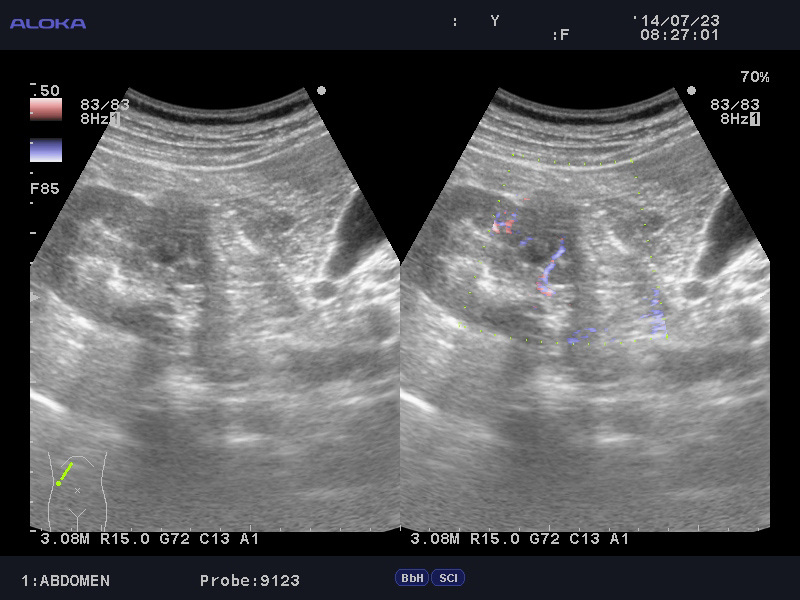

Образование в правой почке

Мужчина средних лет.Жалоб не предъявляет.

С его слов, 10 лет назад в правой почке находили кисту.

Сканер Sonoscape S40

Aloka alpha 6

Ваше мнение?

гипоэхогенное образование в среднем сегменте, деформирующее контур почки...наверное рак

Кровотока ни грамма- Киста